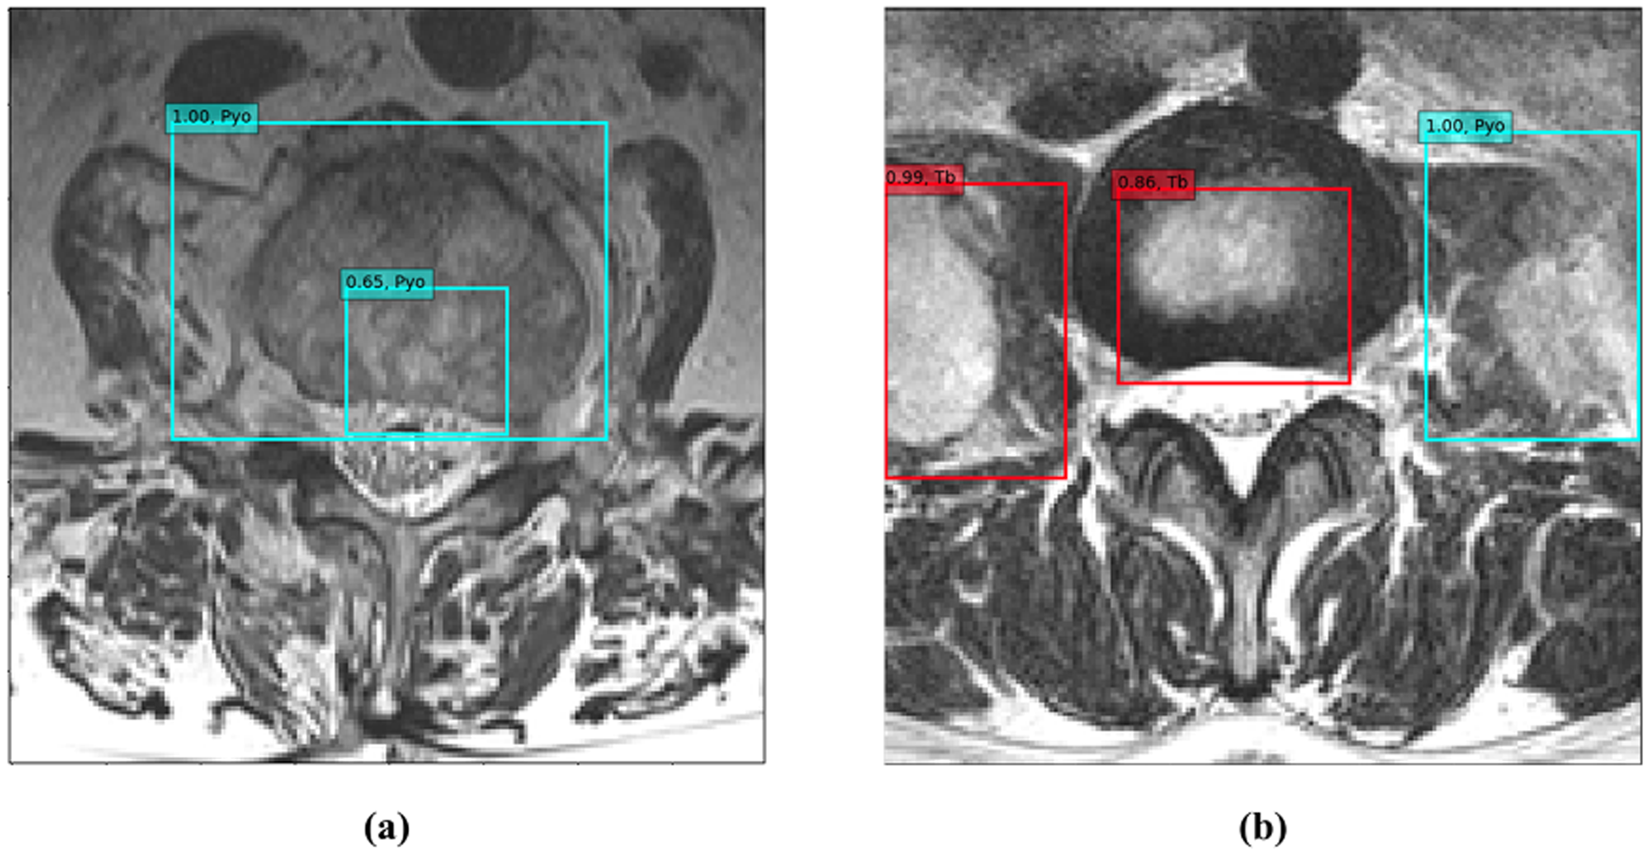

Figure 4

Two examples of probability measurements within each image. (a) A 72-year-old woman with pyogenic spondylitis. Sky-blue boxes indicate pyogenic lesions detected by the deep convolutional neural network classifier. The probability of pyogenic spondylitis for this image is 1.00, which is the highest value among the detected pyogenic lesions. Because no tuberculous lesion is observed, the probability of tuberculous spondylitis is 0. (b) A 31-year-old woman with tuberculous spondylitis. Two red boxes indicate tuberculous lesions and a sky-blue box indicates a pyogenic lesion. The probability of tuberculous and pyogenic spondylitis is 0.99 and 1.00, respectively. Abbreviations: Pyo, pyogenic spondylitis; Tb, tuberculous spondylitis.